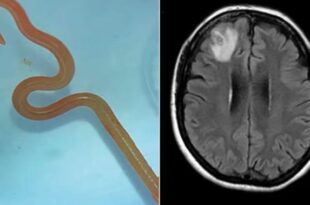

Vierme viu, de 8 centimetri lungime, găsit în creierul unei femei

Un pacientă Australia, în vârstă de 64 de ani, se plângea de ceva vreme de pierderi de memorie, iar surpriza neurochirurgului a fost să găsească un parazit care infectează de obicei pitonii. Australianca în vârstă de 64 de ani suferea de depresie şi de deficienţe de memorie de ceva vreme, iar cauza nu ar fi putut fi imaginată niciodată: un …